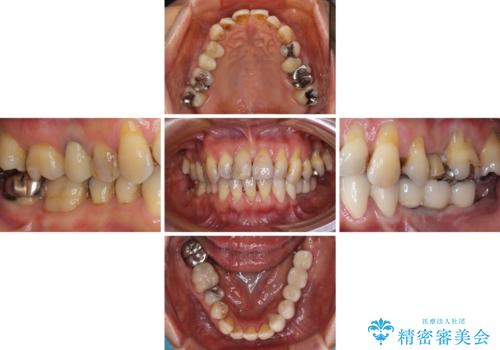

- 義歯を使いたくないものの、骨の幅が狭くインプラント治療を断られているとのことで来院された患者様です。

レントゲンやCTより、骨の高さと幅が不足しており、骨を増やす必要のある状態でした。

しかしながら、全身疾患により骨造成術の予後に不安があったため、デンサーバー(Densah ® Bur)という骨幅を増大することが可能なドリルを用いてインプラントを埋入することとしました。

入れ歯の支台となっていたコーヌスのゴールドも除去し、インプラント部と合わせてオールセラミッククラウンにて補綴治療を行うこととしました。

インプラント埋入後、必要以上に傷口に歯ブラシを当てすぎてしまったことで歯肉の炎症が続き、それに伴いインプラント周辺の骨が若干吸収してしまいました。それでも術後の経過は良好で、違和感や不具合なく使用できています。